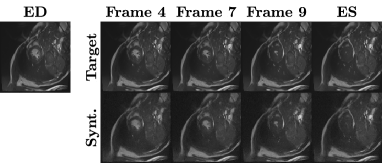

Iconic advancements of generative models in the medical domain have been possible due to several factors, such as state-of-the-art computational hardware and, more importantly, the availability of medical datasets (both open and in-house). Hence, promising solutions for medical image synthesis, restoration, acceleration, and many other tasks have been proposed over the past few years [19]. Recent efforts to generate longitudinal medical images were mainly proposed for the following two tasks: 1) generation of longitudinal brain image [16], which takes a source brain image and generates a new image with respect to chronological age (i.e., normal) progression or disease (i.e., abnormal) progression [11]; and 2) generation of multi-frame cardiac image [4, 12], which typically take a starting frame of a cardiac cycle (i.e., end-diastolic or ED phase) and generates the final frame of the cycle (i.e., end-systolic or ES phase). An illustration showing examples of these tasks is presented in Fig. 1. Generative adversarial networks (GANs) have been a de facto standard for these tasks in the past few years, but recent advances in diffusion models have shown promising results. For example, the latent diffusion model, which uses the latent embedding of an image as input to the diffusion model to improve computational efficiency, has been used to synthesize high-quality 3D brain MRI [17]. Similarly, a diffusion model was combined with a deformation image registration model, namely VoxelMorph [2], to synthesize the end-systolic frame of cardiac MRI [12, 13]. However, most of these works rely on the input from a single image to generate its longitudinal images. Even when longitudinal samples are available, these methods often ignore the sequential dependency in the medical domain.

Refer to caption

(a) Longitudinal Brain MRI

(b) Multi-frame Cardiac MRI

Figure 1: Examples of longitudinal medical images synthesized by our proposed SADM.